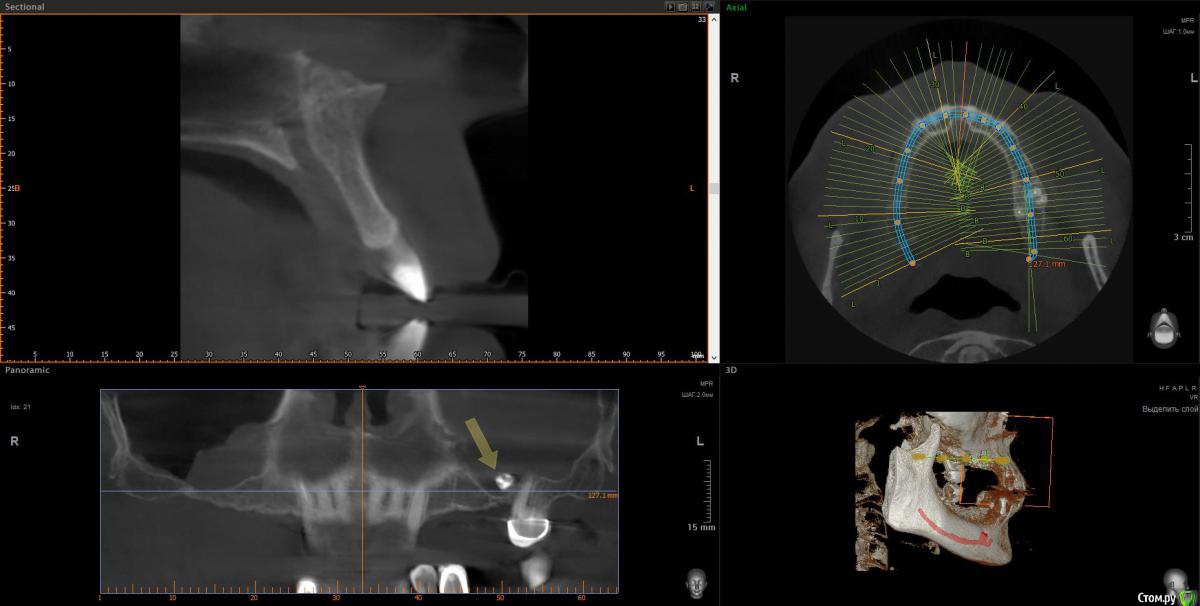

wladdX Опубликовано 9 апреля, 2018 Поделиться Опубликовано 9 апреля, 2018 Несколько скриншотов 2 Ссылка на комментарий

Irouil Опубликовано 10 апреля, 2018 Поделиться Опубликовано 10 апреля, 2018 1. Внизу справа можно имплантироваться, мягкотканную пластику провести нужно будет только 2. В пазухе слева живёт грибок, надо удалять независимо от вида имплантации на верхней челюсти 3. Про зигомы надо ещё КТ самих скул 4. С трефоилом знаком только по наслышке, но он используется (вроде бы) только на нижней челюсти, там необходимости его я не вижу. Коллеги, что знакомы с ним лучше, могут поправить. 1 Ссылка на комментарий

Irouil Опубликовано 10 апреля, 2018 Поделиться Опубликовано 10 апреля, 2018 Спасибо,уважаемые доктора,в пазухе слева дентин.Там пломбировочный материал, возможно искусственный дентин, грибковое тело растет на немА мягкотканная пластика проводится одновременно с установлением имплантов?ДаДля установки имплантов внизу справа сколько их нужно и должны ли они быть меньшего размера из-за атрофии костной ткани?Меньшего чем что? Чем Ваша челюсть? безусловно. В остальном, по моему мнению, установить Вам имплантаты с покрывающими необходимости размерами особых препятствий нет. Нужно два имплантата установить. А импланты внизу слева- сколько их нужно- один или два? С нетерпением жду ответа.Зависит от того, сколько и что будет наверху. 1-2 1 Ссылка на комментарий

Bier Опубликовано 11 апреля, 2018 Поделиться Опубликовано 11 апреля, 2018 я бы думал про установку по паре имплантатов с каждой стороны на каждой челюсти. Слева внизу не вижу состояния зуба, скриншота нет.Внизу справа можно имплантировать, левую пазуху обязательно чистить.О зигомах или трефойле думать рановато, это радикальные вещи уже. Сначала пазуху почистить, потом поставить имплантаты внизу, потом заниматься верхом. 1 Ссылка на комментарий